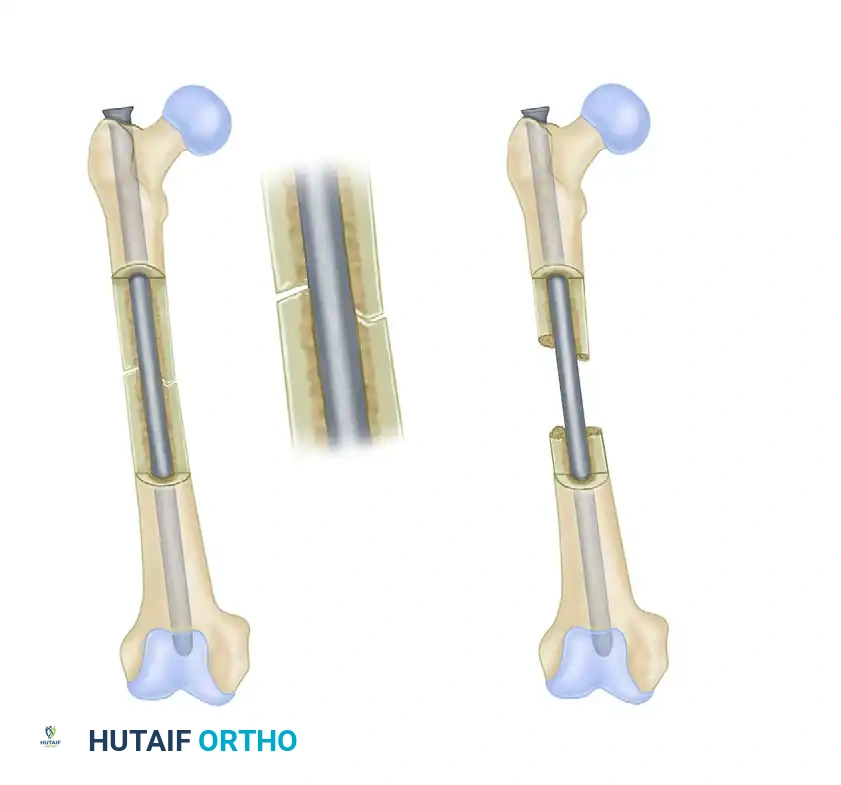

FIGURE 53-36: Dynamic (A) and static (B) locking of an intramedullary nail. Dynamic locking allows for controlled axial compression, whereas static locking rigidly controls both length and rotation.

- Static Locking: Involves placing screws in round holes at both the proximal and distal ends of the nail. This configuration locks the bone to the nail entirely, preventing any axial shortening or rotational movement. It is mandatory for comminuted, spiral, or bone-loss fractures where maintenance of limb length is critical.

- Dynamic Locking: Involves placing a screw through a slotted hole at one end of the nail, allowing the bone fragment to slide axially along the nail while still preventing rotation. This allows contact-compression forces to impact the fracture surfaces during weight-bearing—a highly desirable physiological stimulus for bone union. Dynamization can be performed as a secondary procedure (removing static screws to allow a slotted screw to slide) if delayed union is observed.

In highly comminuted fractures, static locking with multiple distal and proximal screws is essential to maintain length and prevent rotational collapse during the early phases of healing.